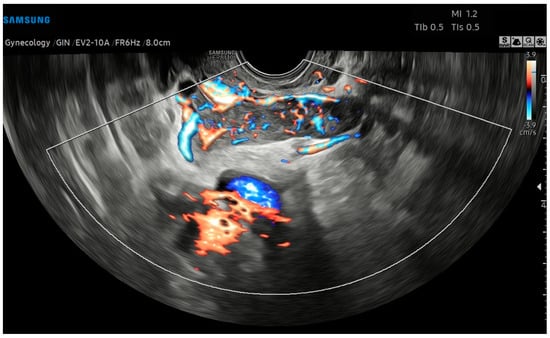

A 43-year-old healthy woman was referred to our Hospital in September 2022, following menometrorrhagia, pelvic pain and a recent diagnosis of uterine fibromatosis. Informed written consent for the publication of data was obtained. An expert transvaginal ultrasound with the Samsung HeraI10 was performed, revealing an enlarged, globose-shaped uterus, with a transmural (FIGO 3-5) uterine mass of the posterior body–fundus wall, which was hypoechoic, non-homogeneous, and without calcifications, cystic areas, or acoustic shadows, measuring 8.8 × 7.9 × 6.4 cm, and highly vascularized (Color Score 3-4, CS3-4), at the Color Doppler (CD) analysis (Figure 1).

Figure 1. Transvaginal ultrasound with Color Doppler analysis. (A) Longitudinal plane; (B) axial plane showing a hypoechoic, heterogeneous uterine mass, without calcifications or acoustic shadows, measuring (L × H × W) 8.8 × 7.9 × 6.4 cm. The Color Doppler analysis reveals an abundant perilesional and intralesional vascularization.